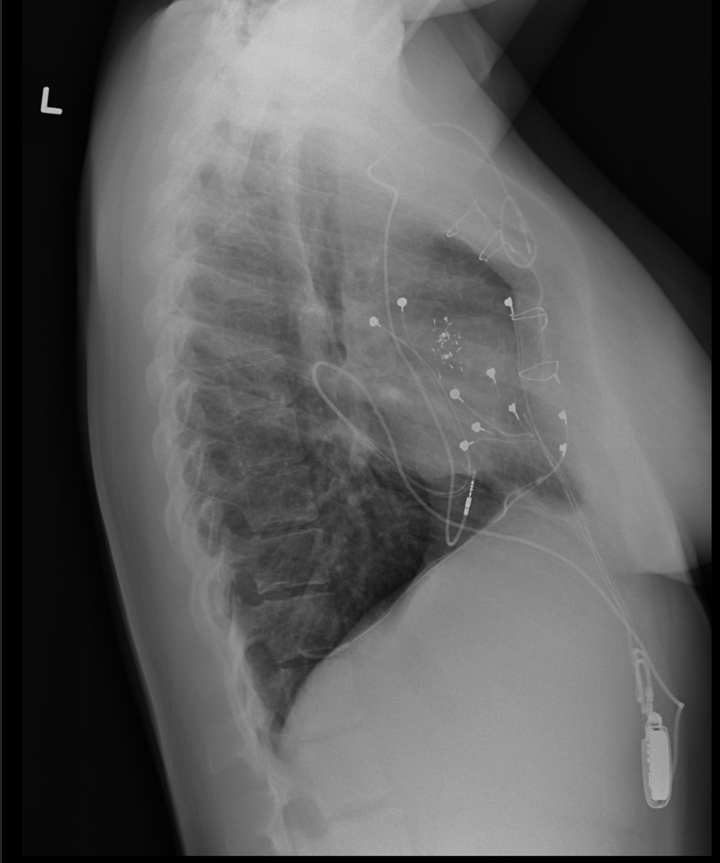

Later that evening within the nursery, a nurse seen my pores and skin had turned blue. That single statement saved my life. Realizing one thing was very incorrect, the hospital ordered a chest X-ray and put me in an ambulance to Upstate Medical in Syracuse. That evening, I had my first coronary heart catheterization: a short lived, lifesaving measure to let oxygenated and non-oxygenated blood combine sufficient to maintain my organs working.

The analysis was tricuspid atresia — I’d been born with just one functioning ventricle, a uncommon congenital coronary heart defect. My coronary heart actually wasn’t constructed to maintain life.

At eight years previous, I had my third open-heart surgical procedure — this time, to “tune up” my Fontan and implant my first pacemaker. That pacemaker lasted till I used to be 12, when scar tissue shaped on the leads and stopped {the electrical} pulses that saved my coronary heart beating. Cue open-heart surgical procedure quantity 4 for my second pacemaker.

They implanted the brand new pacemaker transvenously by threading the leads by way of my veins into my coronary heart. That one additionally developed scarring on the leads, that means the generator had to get replaced each three to 5 years as a substitute of the standard 10.

Dr. Jonas had a brand new thought: place the pacemaker lead in a particular space of my coronary heart to stop scar tissue from forming.

Picture Courtesy Of Livia Cucchiara